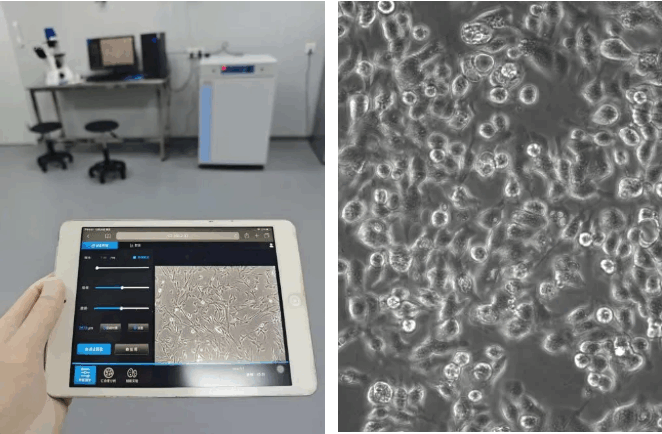

Ã÷ÃĀģîŧ°ûŗÉĪņxŋÉéLrégo¸É_Ķ^yÄ[Áöŧ°ûÔöÖŗĄĸßwŌÆĩČĐĐéŖŦŊYēĪož˛ŲŋØšĻÄÜŖŦéŋš°ŠËÎīēYßxÅcCÖÆŅĐžŋĖᚊ¸ßЧÆŊÅ_ĄŖ

Ã÷ÃĀÅÄČéĪŲ°Šŧ°û

02°Šŧ°ûÅāđBŅĐžŋĶ^y

ģîŧ°ûŗÉĪņx+ÆŊ°å/ĘÖCŖŦožßBŊĶŖŦąÜÃâÎÛČžŖŦŧ¯ŧsģ¯ÅääļāˇNŗÉĪņšĻÄÜĄŖ